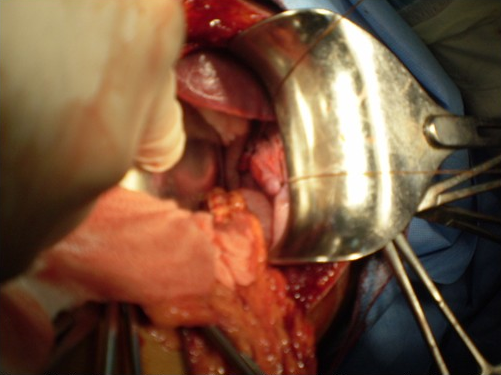

Sutura de la brecha diafragmática con material irreabsorbible a puntos separados; con la última lanzada en el diafragma se solicita reexpansión pulmonar con hiperpresión. (Figura 2).